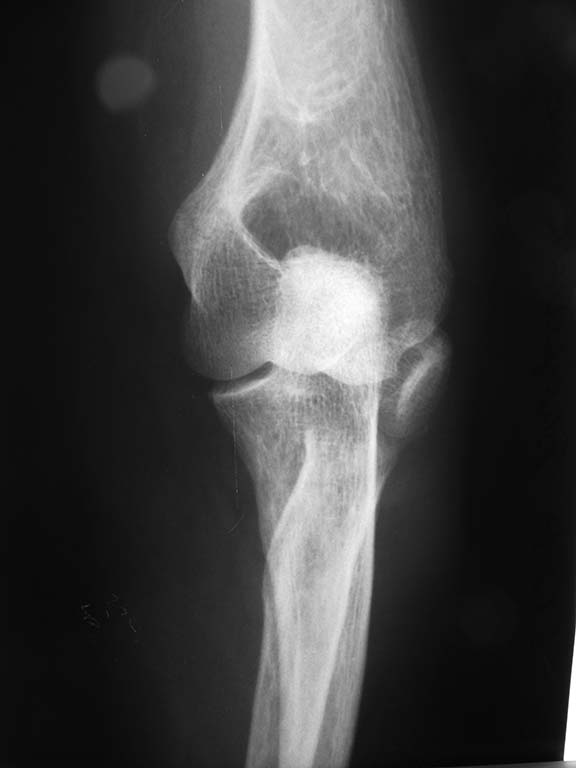

Здравствуйте, всем доброй ночи. Поступила женщина 50 лет. Перелом шейки лучевой кости слева. Чрезмыщелковый перелом плеча слева. Перелом лучевой кости слева со смещением+ шиловидный отросток локтевой кости.

Перелом мыщелков установлен автором сообщения, по снимкам во вложении его также можно предположить

Перелом головки луча с полным ее смещением и разворотом ее под углом 90 градусов

Протезирование головки возможно более перспективно в плане функции, хотя будет интересно услышать мнение коллег

Чрезмыщелкового перелома плеча не видно.. Головку лучевой вернуть на место и синтезировать (если есть чем). Дистальный луч то же синтезировать.

Много смотрел - множественных переломов локтя не обнаружил. Боюсь показаться глупым, но на мой взгляд головку луча можно вернуть на место путём открытой репозиции без обширных диссекций. Вариант фиксации, по-моему мнению - ретроградный ИМО. Я бы выбрал два TEN 2,5-3 мм. Остеопороза не видно. Женщина не старая. Эндопротезирование никуда не денется. Дистальный луч можно по-всякому стабилизировать. С уважением!

Совершенно верно, уважаемый Сергей Юрьевич. Ретроградно, можно и через дистальный отломок луча с предварительной его репозицией. У детей с подобными переломами такое получается. Головка по предъявленным снимкам сломана субкамитально, отломок - вся головка + развёрнута на 90 градусов. Можно, конечно, репонировать закрыто с джойстиком или леватором. Нейлинг, на мой взгляд, совсем не ухудшит судьбу головки и позволит как можно раньше начать движения в суставах предплечья.